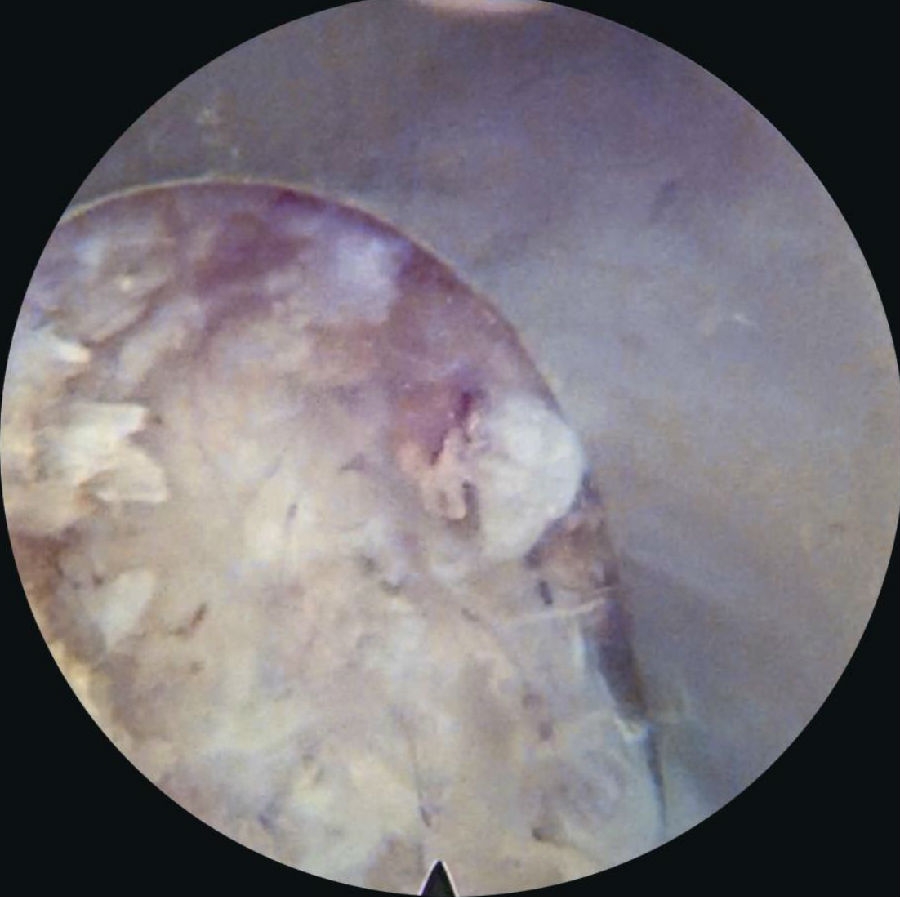

8. 镜下操作

采用一次性双极射频手术刀头、Punch钳、小直钳、磨钻依次切除或修整部分肥厚或钙化的黄韧带、椎体后缘增生的骨赘、椎体后缘对神经根造成压迫的外层纤维环及其边缘的硬化或骨化结构、与后纵韧带粘连的增生结缔组织,对神经根背侧和腹侧进行全面的减压松解,特别是神经根下方的微小硬化性组织。(图16~图21)

图16 内镜下显示套管内视野中间纤维环

图17-图20 内镜下显示套管内视野中间纤维环;内镜下小直钳取髓核;取出部分髓核后张力下降,神经张力间接下降;转动工作套管显露硬膜囊和周围组织

5. 黄韧带扩孔,直视镜下沿黄韧带裂隙将锥形工作套管轻柔地旋转入椎管,可见破碎的髓核组织及纤维环组织。(图30~图35)

6. 确定髓核组织后,用镜下髓核钳将突出髓核组织切除(图36~图40),直至清晰地看到后纵韧带和神经根周围脂肪组织。